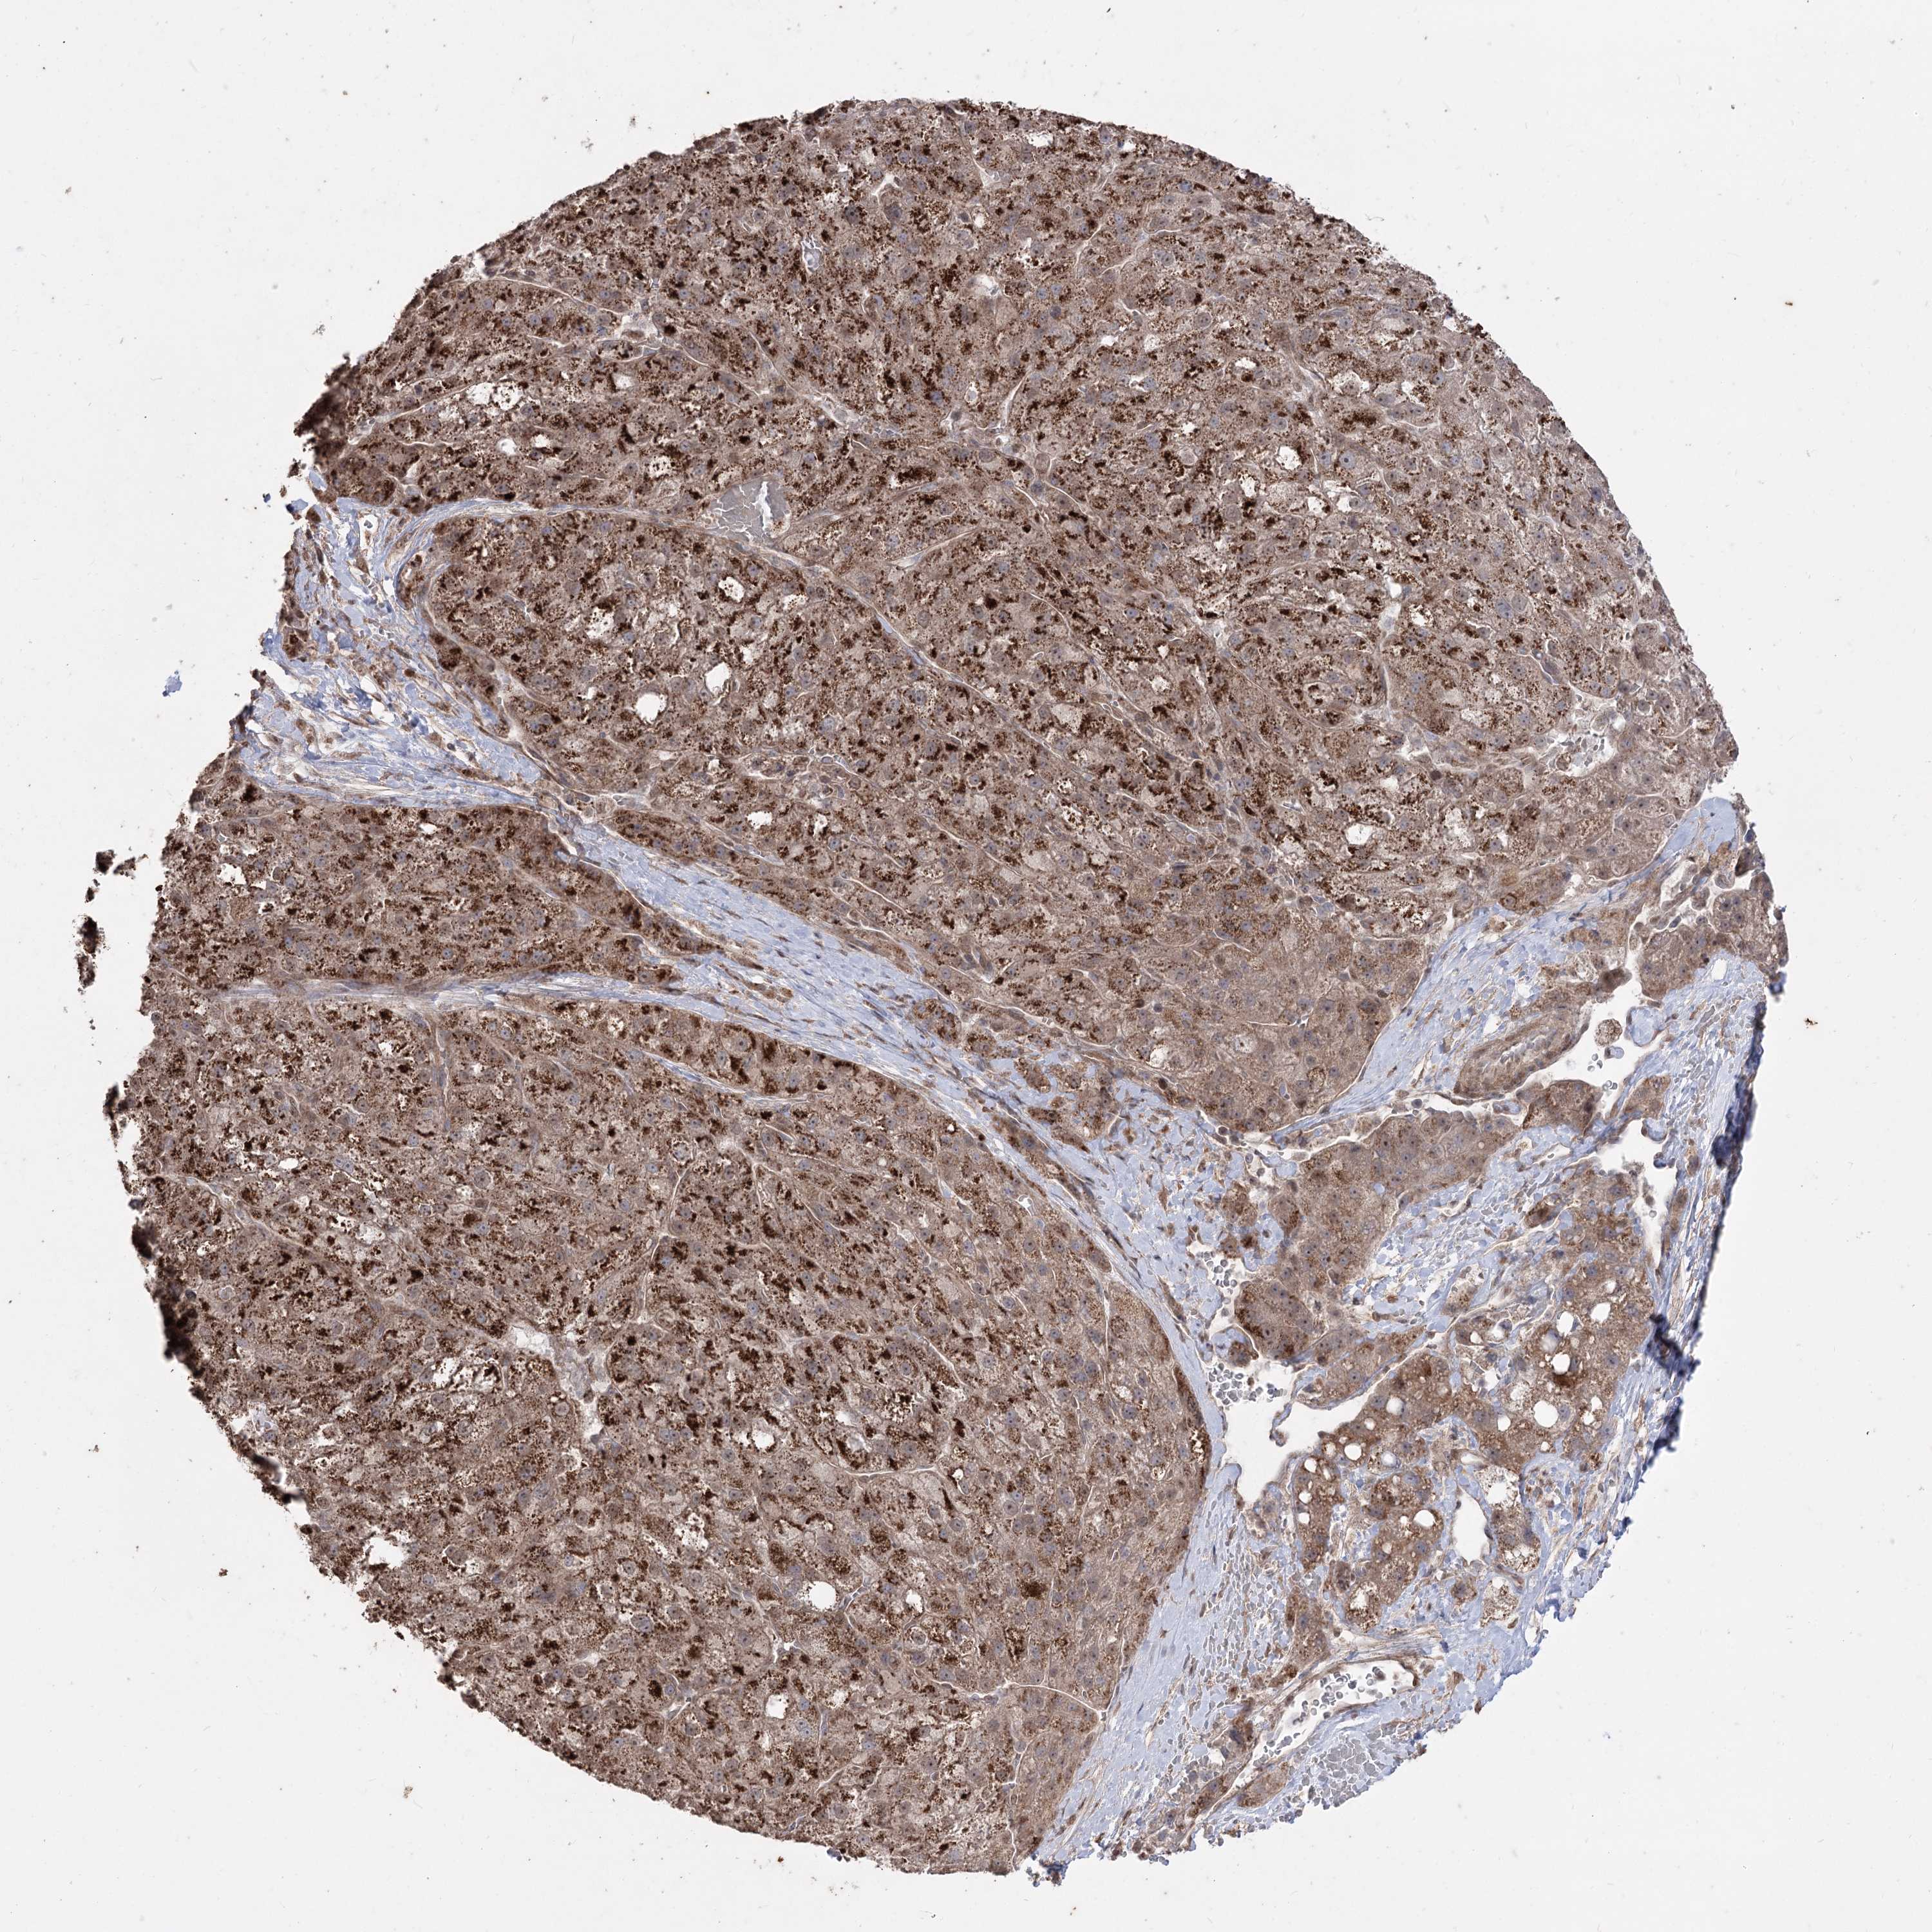

LIVER CANCER - Protein expressioni

A mouse-over function shows sample information and annotation data. Click on an image to view it in a full screen mode. Samples can be filtered based on level of antibody staining by selecting one or several of the following categories: high, medium, low and not detected. The assay and annotation is described here.

Note that samples used for immunohistochemistry by the Human Protein Atlas do not correspond to samples in the TCGA dataset.

Antibody stainingi

Antibody staining in the annotated cell types in the current human tissue is reported as not detected, low, medium, or high, based on conventional immunohistochemistry profiling in selected tissues. This score is based on the combination of the staining intensity and fraction of stained cells.

Each image is clickable and will lead to virtual microscopy that enables deeper exploration of all samples and also displays staining intensity scores, fraction scores and subcellular localization as well as patient and tissue information for each sample.

Antibody HPA035959

Antibody HPA035960

Staining

High

Medium

Low

Not detected

Intensity

Strong

Moderate

Weak

Negative

Quantity

>75%

75%-25%

<25%

None

Location

Nuclear

Cytoplasmic/membranous

Cytoplasmic/membranous,nuclear

Cholangiocarcinoma

Carcinoma, Hepatocellular, NOS